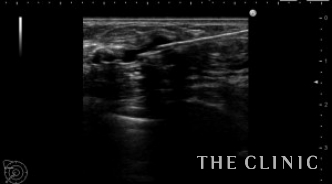

今回は石灰化は治療せず、オイルシストのみ穿刺吸引しました。

吸引したオイルです。